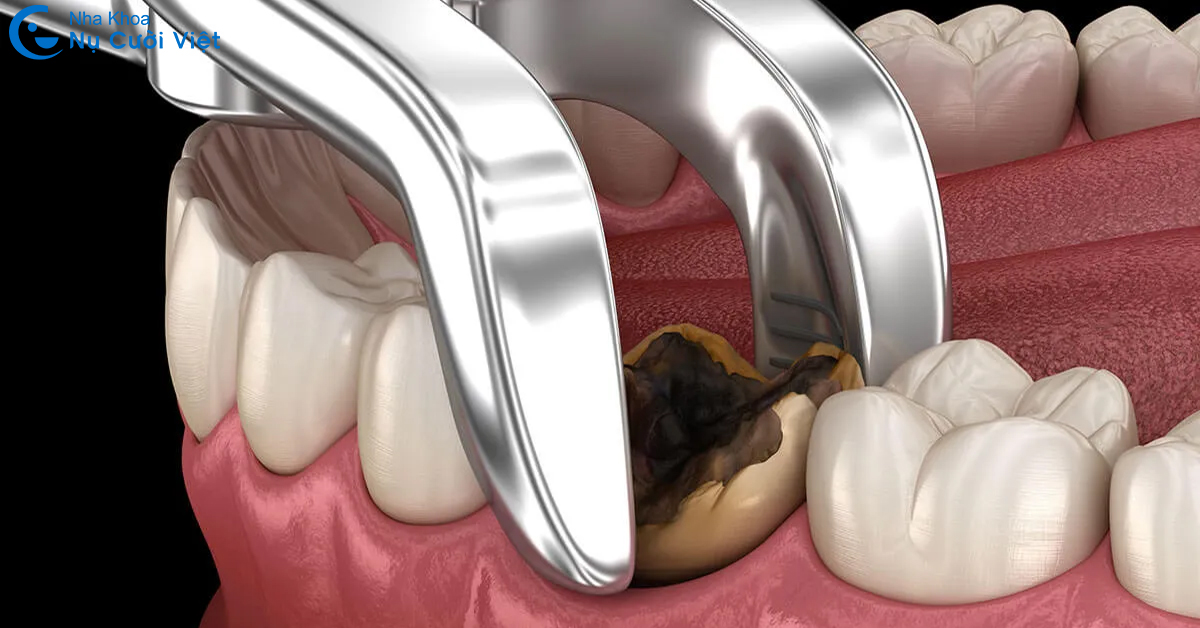

Răng sâu nặng, viêm tủy lan rộng: Khi mô răng bị phá hủy nghiêm trọng, không thể điều trị bằng trám hoặc chữa tủy, bác sĩ sẽ chỉ định nhổ để loại bỏ ổ viêm và tránh lây lan sang các răng khác.

Răng gãy, vỡ không thể phục hồi: Nếu răng bị chấn thương, nứt dọc chân hoặc vỡ sát nướu, việc giữ lại là không khả thi. Nhổ bỏ giúp tránh viêm nhiễm và tạo điều kiện thuận lợi cho trồng răng Implant.

Việc nhổ răng cần được thực hiện trong điều kiện vô trùng, bởi bác sĩ chuyên khoa có kinh nghiệm để đảm bảo an toàn, giảm đau và giúp vết thương nhanh hồi phục.